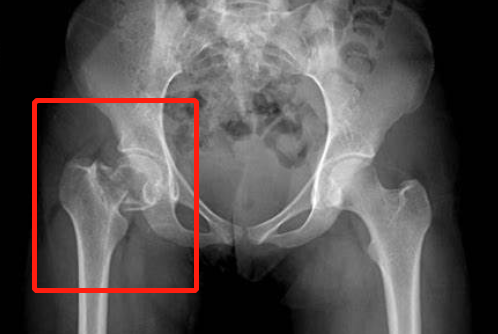

在眾多骨折中,特別是髖部骨折有非常高的致死率和致殘率。在很多醫(yī)生看來,髖部骨折可以稱之為人生中最后一次骨折,因為發(fā)生這種骨折之后,很多患者都因此而致死。